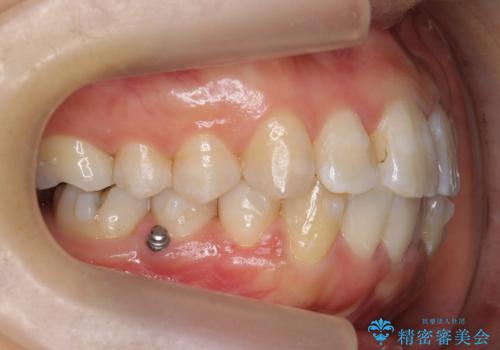

- 歯並びを主訴に来院。

左上2番は以前抜歯したとのこと。

奥歯を後ろに下げて、前歯を並べています。

マウスピースと矯正用のミニスクリューを使用して治療しています。

右下7は根管治療をおすすめしましたが、患者様のご希望により抜歯となり、そのスペースを利用して下の前歯をならべています。